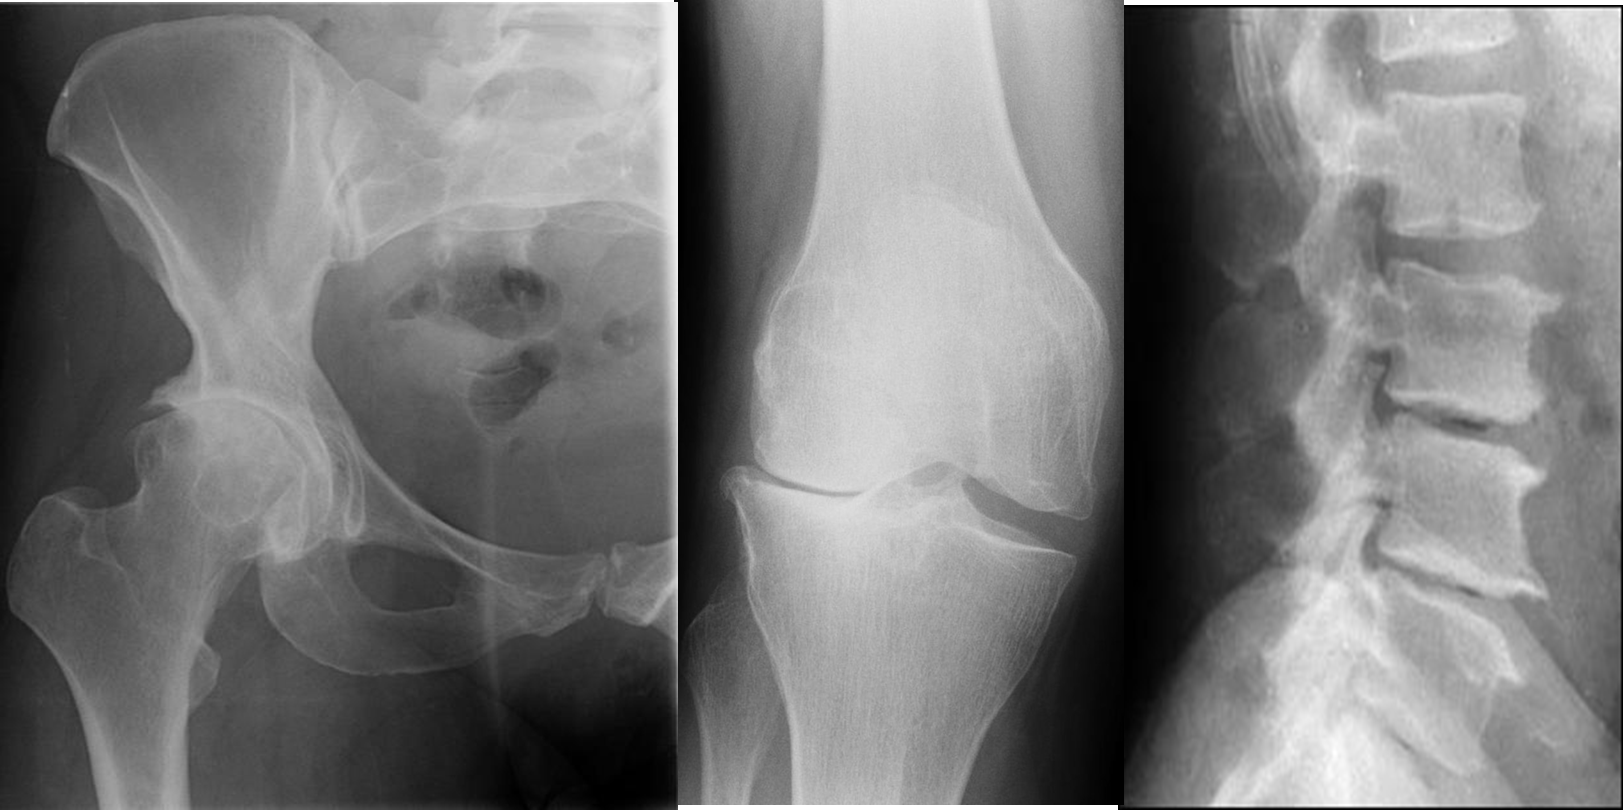

Radiological signs of osteoarthritis

Irregular joint space narrowing

Subchondral sclerosis: a dense area of bone (visible on x-ray) just below the cartilage zone of a joint.

Osteophytes (bone spurs): spurs or densifications that develop on the edges of the joint.

Subchondral cyst: a fluid-filled cyst that develops on the surface of a joint

Lateral compartment osteoarthritis of the knee X-ray right knee (AP view) Marked lateral compartment narrowing is accompanied by subchondral sclerosis and osteophyte formation. Tibial spine osteophytes are also visible.

Degenerative disease of spine with osteophyte formation and vacuum disc phenomenon.